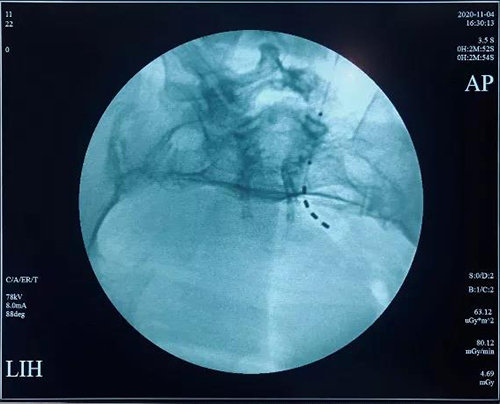

近日,依托山东省疼痛医学会泌尿生殖专业委员会,山东第一医科大学附属省立医院(山东省立医院)泌尿外科牵头,在全省范围内联合12家地市级医院泌尿外科成立了神经源性膀胱单病种多中心协作联盟,旨在对神经源性膀胱开展规范化诊疗及临床研究。同时,预启动了骶神经调控技术(SNM)治疗神经源性膀胱(NB)疗效的前瞻性随机对照研究,探讨了研究的目的、方法、入组及排除标准、疗效判定等问题。

省立医院神经源性膀胱诊疗MDT还与北京医院泌尿外科、北京博爱医院泌尿外科山东大学第二医学尿动力学研究室建立广泛深入的合作关系。启动会还邀请北京医院著名尿控专家张耀光教授进行了神经源性膀胱患者骶神经调控的手术演示以及专题讲座。山东大学第二医院的张秀琳教授就神经源性膀胱的尿流动力学的表现做出了解析。